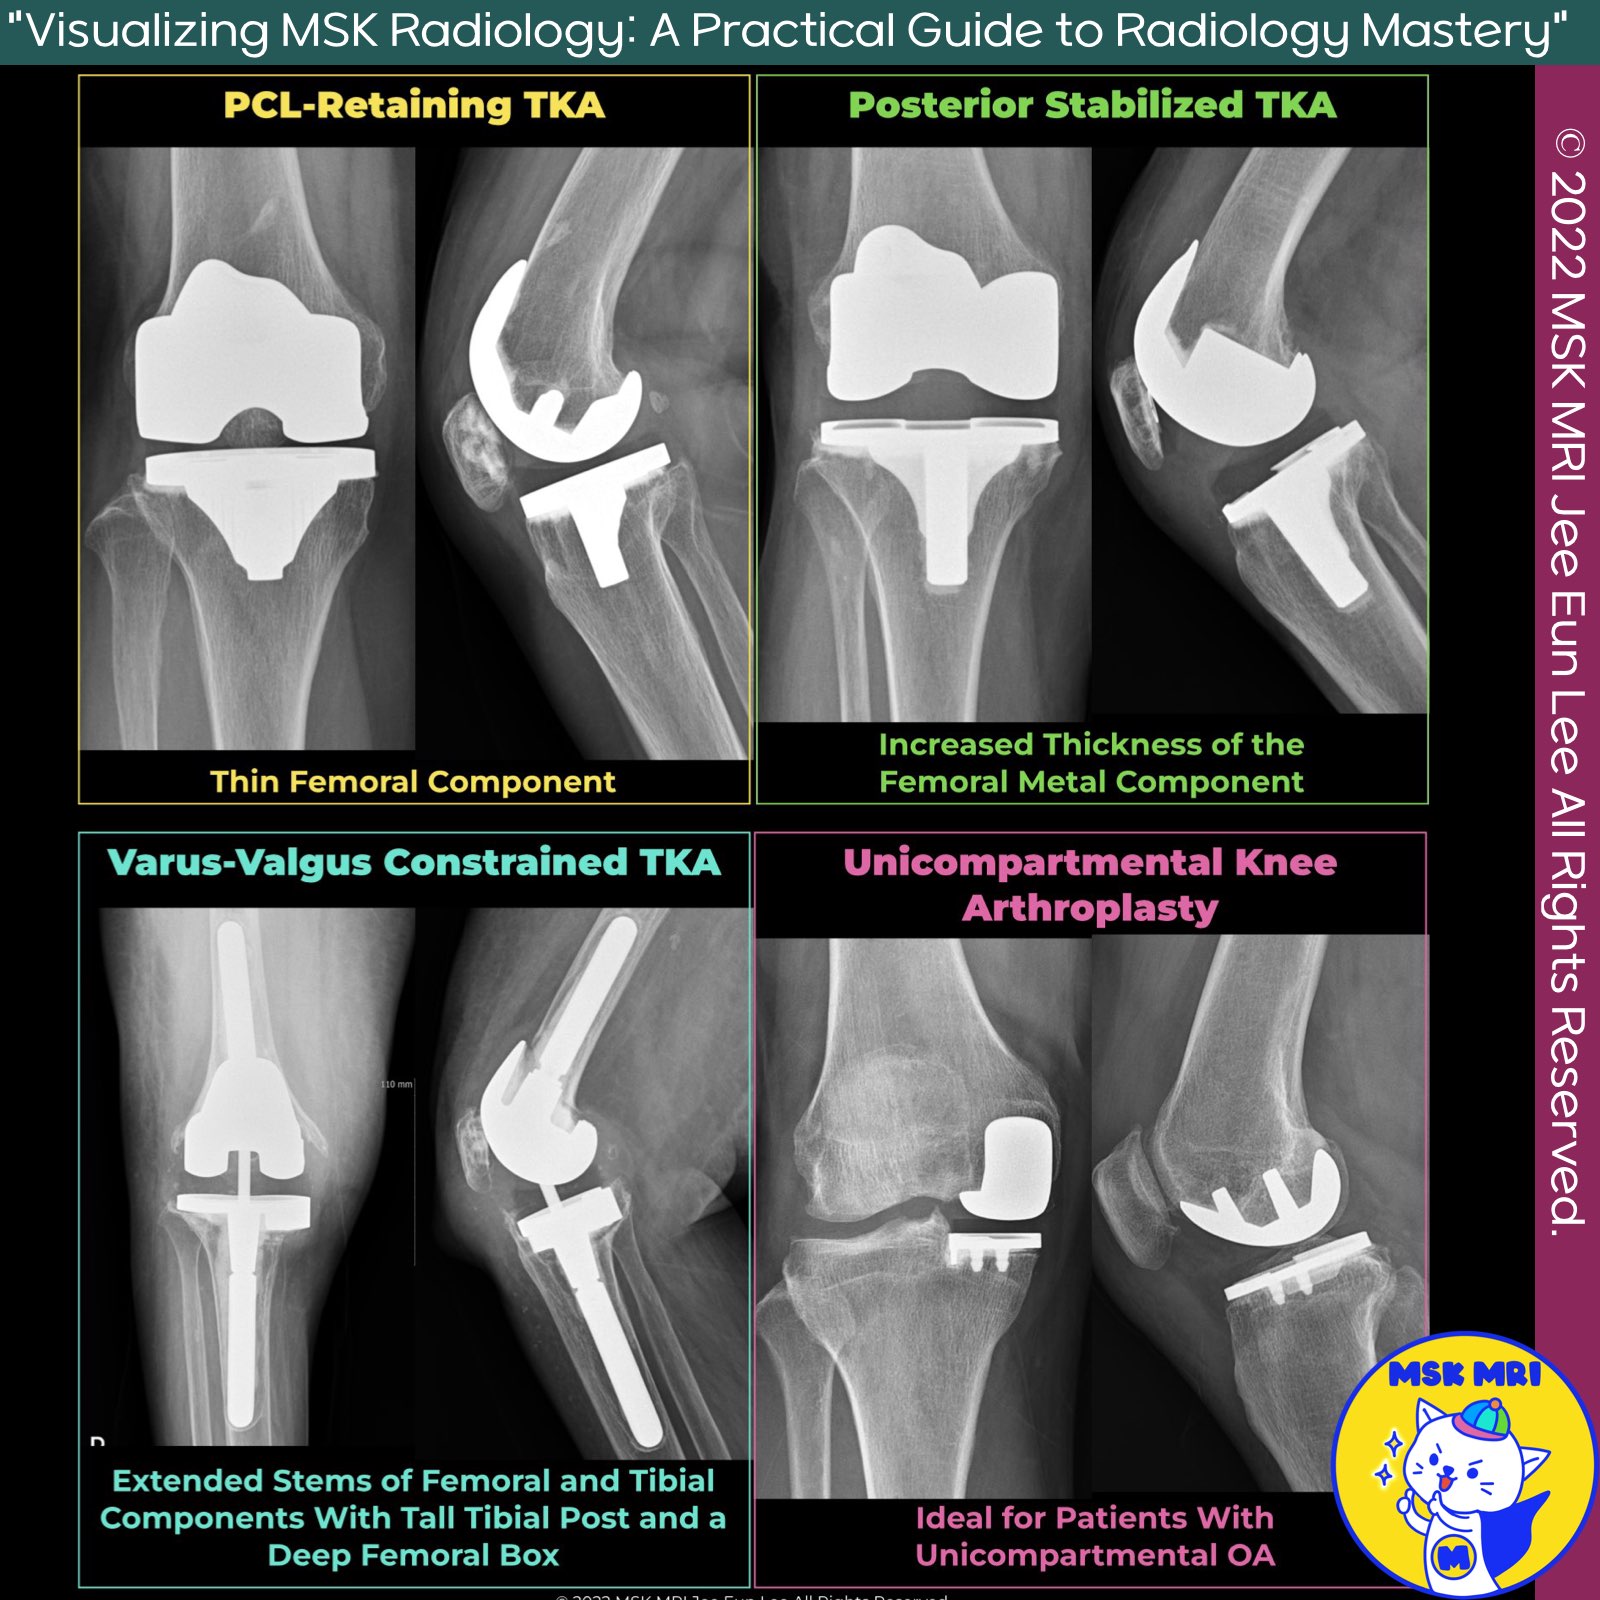

📌 Surgical Options for Knee Arthroplasty

1. PCL-Retaining TKA

- In PCL-retaining TKAs, the tibial and femoral metal components preserve the native PCL, providing stability.

- Suitable for patients with adequate bone stock, intact soft tissues, and an intact PCL.

2. Posterior-Stabilized TKA

- Posterior-stabilized TKAs replace the function of the PCL, preventing anterior translation of the femur on the tibia during flexion.

- These provide stability by limiting posterior motion in flexion.

- They offer increased range of motion without significant differences in complication rates compared to PCL-retaining TKAs.

3. Varus-Valgus Constrained TKA

- Varus-valgus constrained implants, with a tall tibial post and deep femoral box, provide stability in the coronal plane.

- They are used for severe valgus deformities, collateral ligament deficiency, bone defects, and residual instability.

4. Unicompartmental Arthroplasty

- This procedure resurfaces the articular surfaces of a single compartment, commonly the medial compartment, making it ideal for patients with unicompartmental OA.